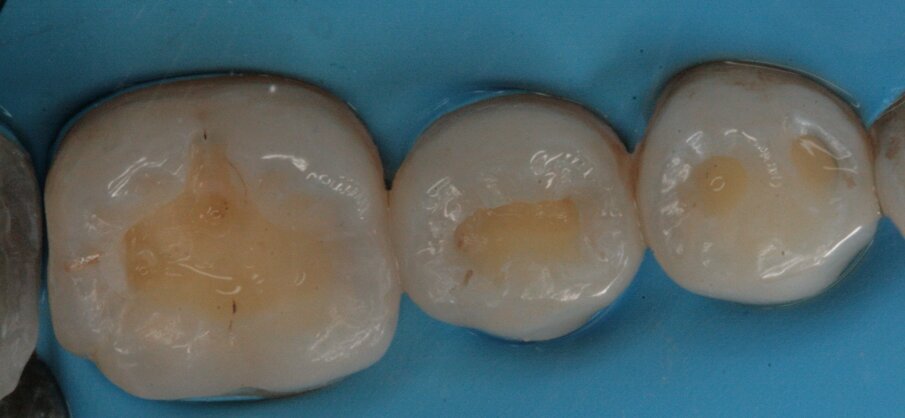

Gli elementi da trattare erano il 27, 26, 25 e 24 (Figg. 12-14); esattamente come per il settore 1, alcune lesioni cariose si approfondivano in dentina mentre altre (24, 25) rimanevano confinate allo smalto permettendo cosi una cura precoce della patologia e l’esecuzione di un’odontoiatria minimamente invasiva per preservare al meglio il tessuto smalteo (Figg. 13-18).

Fig. 13_Restauro presente sul 25.

Fig. 14_Isolamento sotto diga di gomma del settore 2.

Figg. 15, 16_Preparazione delle cavità.

Figg. 17, 18_Restauri delle cavità.